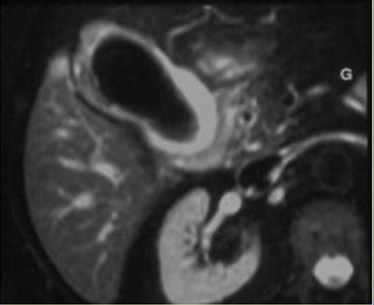

Image

radiologque IRM en coupe axiale : La vesicule

biliaire est distendue , sa paroi est tres epais |

Image radiologique IRM ponderee en T2 :

Cholecystite lithiasique aigue avec vesicule

biliaire

distendue , epaissisement de la paroi vesiculaire ,

oedeme de la sous sereuse et images des calculs a la

fondus de la vesicule biliaire |